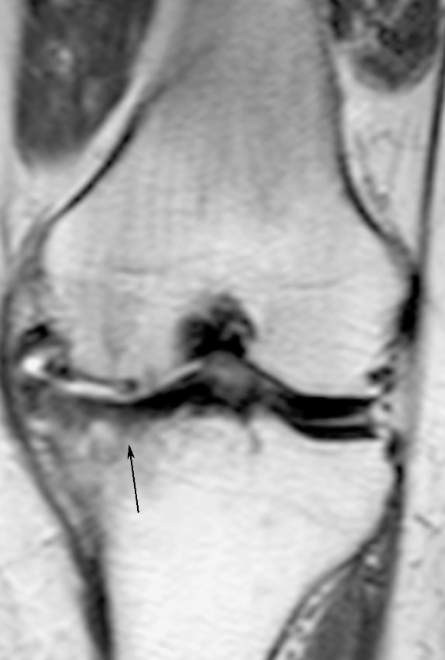

关节软骨皱褶或连续性中断,中等信号的关节软骨内有高信号区,甚至关节软骨及软骨下骨塌陷呈阶梯状,软骨下骨松质内可见局部水肿和出血(图6),可合并软骨下骨关节内骨折。如有软骨撕脱,可形成关节内游离体。

图6 关节软骨损伤冠状位T1WI示胫骨内侧髁关节软骨缺失,骨性关节面欠光滑,关节面下骨质内见大片状稍长T1信号影。